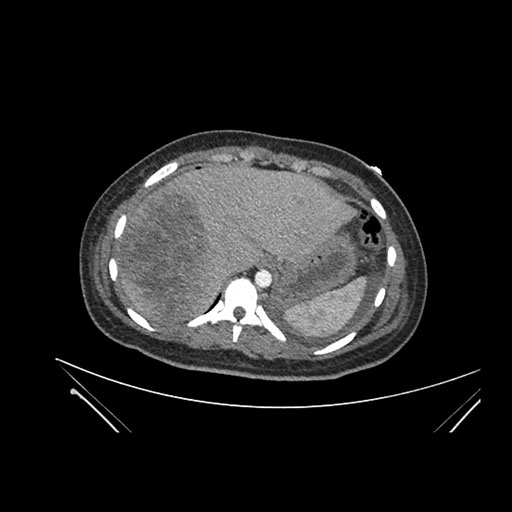

Look through the patient's CT scan to identify any areas of concern for the necessary procedure.

Imaging analysis

Based on initial findings, which issue(s) would you be most concerned about?